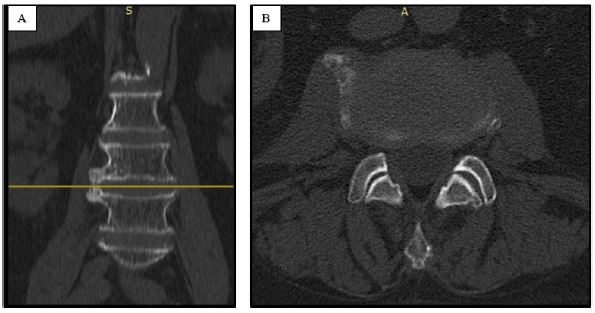

The patient was discharged at home on the second day after the operation. He reported complete relief of pain immediately after the procedure, and at the 6-week follow-up, he was still pain-free. A lumbar computed tomography revealing the absence of the osteophyte was performed 6 weeks after the operation (Figure 4A).

Figure 4: The follow-up lumbar computed tomography, 6 weeks after the operation revealing the absence of the osteophyte: coronal (A) and axial planes (B).